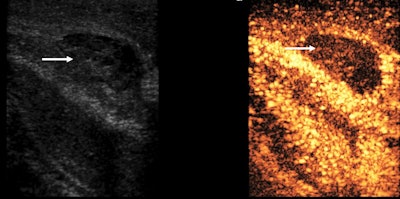

The authors recommend a split-screen approach, with B-mode and CEUS images displayed side-by-side, allowing low mechanical index (MI) B-mode images to localize the area of interest, and they propose a dose of 4.8 ml of SonoVue/Lumason. A CEUS examination requires intravenous access for contrast administration, with a minimum calibre of 18-22-G, and prompt access to resuscitation equipment should be available.

The dynamic range should be wide if fine differences of enhancement are sought, or low to make the blood vessels stand out more brightly for addressing vascular injuries. A frame rate of more than 10 Hz/fps is useful for assessing active bleeding, but this comes at the expense of microbubble disruption. An MI that is too high will cause microbubble disruption, particularly in the near field, whereas an MI that is too low will lead to poor visualization of the far field. Take video clips for reevaluation and avoid prolonged scanning of the same area, the researchers advised.

"The B-mode appearance of a penile hematoma can vary with its age, being hyperechoic in the acute phase and cystic with septations in chronic stages. In the long-term, fibrosis can be developed, appearing as an ill-defined echogenic abnormality," the authors noted, adding that on CEUS, a penile hematoma appears as a non-enhancing area, and it allows a confident diagnosis and a better delineation of the hematoma.